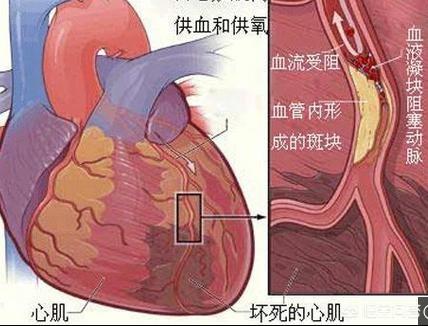

冠状動脈性心臓病は、患者の冠状動脈の血管が何らかの理由で狭窄閉塞し、血液酸素エネルギーの正常な流れに影響を与えるため、胸が締め付けられるような症状を引き起こす可能性があり、患者の日常的な行動が供給よりも多くのエネルギーを消費すると、一連の臨床症状が発生し、胸が締め付けられるような症状は典型的な症状の1つです。

1、冠動脈の急性血栓症と痙攣。冠状動脈性心臓病の大部分の病態生理的基礎は冠状動脈アテローム性動脈硬化症であるが、冠状動脈性心臓病患者の中には冠状動脈のプラークが少ししかなく、狭窄があまり強くなく、狭心症や心筋梗塞さえも冠状動脈内の急性血栓症や冠状動脈の攣縮が原因である。筆者は30代男性の急性梗塞患者に会ったことがあるが、冠動脈の結果はプラークが少ししかなく、冠動脈内の急性血栓と自己溶解が原因であることを考慮した。

2.冠微小血管疾患。冠微小血管疾患(CMVD)とは、様々な病原因子の影響下にある前部小冠動脈および小動脈の構造的および/または機能的異常によって引き起こされる労作性狭心症または心筋虚血の客観的証拠の臨床的症候群を指す。冠動脈には前部小動脈(直径0.1~0.5mm)、細動脈(直径0.1mm未満)、心外膜下冠動脈(直径0.5~5mm)の3つの部分がある。 冠動脈細動脈には前部小動脈と細動脈が含まれ、その構造的・機能的異常も狭心症やその他の臨床症状を引き起こす。